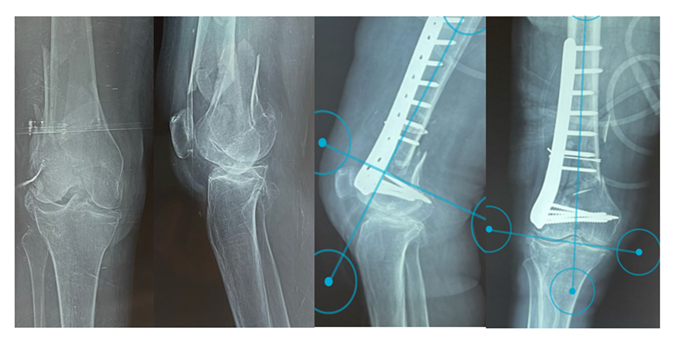

This was an observational and descriptive study. It was conducted on the records of patients hospitalized between July 1, 2023, and June 30, 2024. The patients had DFF on porotic bone (fracture caused by low energy trauma, intraoperative bone fragility), classified according to the criteria of the Association for the Study of Osteosynthesis (AO) [12,13]. Patients with an open or unicondylar fracture were managed using others osteosynthesis material were not included as well as those lost to follow-up or who declined to participate in the study. Fractures were reduced and fixed using a lateral LP (Figure 1). The studied parameters were patient age, gender, previous autonomy, comorbidities, circumstances and mechanism of injury, immediate complications, fracture type, and associated injuries. All procedures were performed under spinal anesthesia, with the patient in the supine position on a standard operating table and the contralateral lower limb supported by a gynecological support.

The series comprised 14 patients: 2 men and 12 women. The male-to-female ratio was 0.16. The mean age was 75.29 years with a range of 61 and 96. All patients had experienced falls from standing height. The right lower limb was affected in the same proportion as the left (n=7). Nine (9) patients had comorbidities: hypertension (n=7), diabetes (n=1), obesity (n=2), knee stiffness (n=1), and hip stiffness (n=1). The mean Parker score was 7.71 with a range of 6 and 9. The fracture type was A2 (n=7), A3 (n=5), C2 (n=1), and C3 (n=1). One (1) patient had an associated obturator foramen fracture. All patients had a fracture associated with gonarthrosis (Figure 1).

Postoperative anatomical axes were identical to those at the last follow-up; the mean aPDFA was 83.07° with a range of 80° and 86°, and the mean aLDFA was 80.93° with a range of 79° and 83° (Figure 1). The mean knee flexion was 97.93° with a range of 50° and 131° (Figure 2). Knee extension was full in all cases. No axial deformity of the limb was observed. The knee was painless (n=11), with mild pain (n=2), and moderate pain (n=1). No knee instability was observed. All patients were satisfied. The mean functional IKS score was 87.1 with a range of 80 and 95. Complications were observed in 4 patients: knee stiffness (n=1), early infection associated to knee stiffness (n=1), leg length discrepancy less than 2 cm (n=1) and ischemic stroke (n=1).